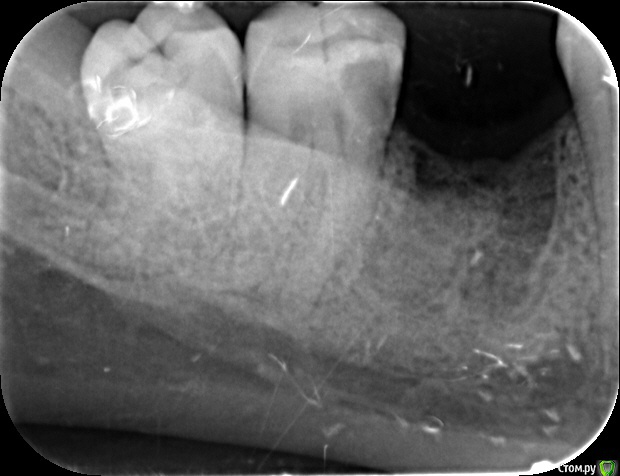

Гарриевич Опубликовано 15 мая, 2015 Поделиться Опубликовано 15 мая, 2015 5 зуб на снимке не виднотут прицельно снимали 7 и 8может Вы имеете в виду 7ку? Ссылка на комментарий

sokolova Опубликовано 15 мая, 2015 Автор Поделиться Опубликовано 15 мая, 2015 так по фото нельзя определить можно или нельзя спасти каналы? Ссылка на комментарий

St. Опубликовано 15 мая, 2015 Поделиться Опубликовано 15 мая, 2015 Нет, окончательно будет видно, только когда Ваш врач уберет все нежизнеспособные ткани. По снимку однозначно определить нельзя. Ссылка на комментарий